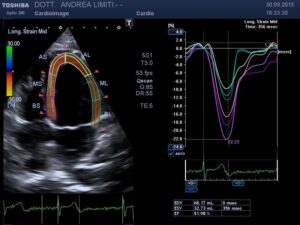

L’ecocardiografia è una metodica nella quale gli ultrasuoni sono utilizzati per visualizzare l’interno del cuore ed il flusso del sangue attraverso le valvole. A differenza delle radiazioni utilizzate in radiologia, gli ultrasuoni sono innocui, per cui non è necessaria alcuna precauzione e l’esame può essere eseguito su qualunque paziente innumerevoli volte (anche nelle donne in gravidanza).

Durante l’esame la sonda viene appoggiata al torace del paziente e gli ultrasuoni vengono diretti all’interno del corpo, senza che il paziente possa avvertirli. Gli ultrasuoni arrivano al cuore e ritornano alla sonda generando echi che sono utilizzati per visualizzare sullo schermo un cuore “virtuale” che ci informa del comportamento del cuore reale del paziente. Le onde sonore possono essere riflesse anche dal sangue in movimento all’interno del cuore e fornire informazioni sul flusso all’interno del cuore e dei vasi.

La visita cardiologica, l’Elettrocardiogramma e l’Ecocardiogramma bidimensionale Color Doppler transtoracico consentono di acquisire una ricchezza di informazioni sullo stato anatomico e funzionale del cuore di livello molto elevato che spesso consentono un primo accurato inquadramento dei problemi cardiologici del paziente. E’ importante tuttavia sapere che, anche con gli apparecchi più avanzati, l’ecocardiografia non offre una valutazione diretta dello stato delle coronarie e quindi l’esame non può essere discriminante per la valutazione di sospetti dolori cardiaci.